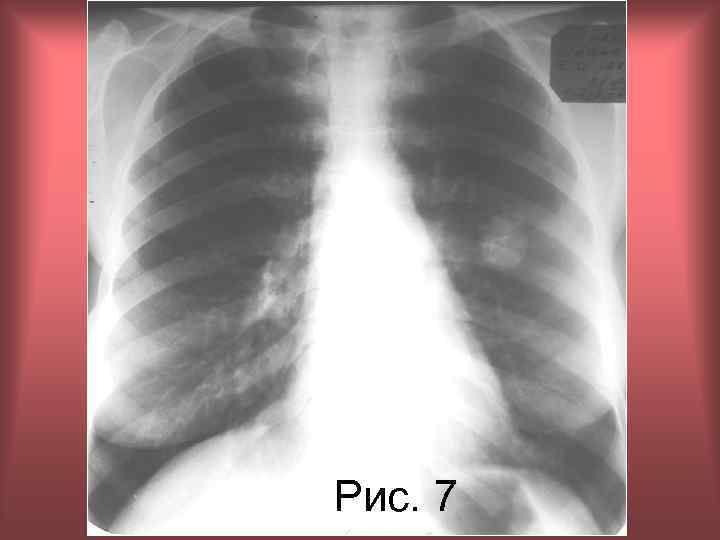

• Пациентка Л. 46 л. Диагноз: Гамартохондрома третьего сегмента левого легкого. Анамнез: длительность наблюдения 5 лет. • Рис. 7. Рентгенограмма органов грудной полости в прямой проекции. • В области третьего межреберья слева определяется шаровидная тень средней интенсивности, неоднородной структуры, имеющая не ровные, четкие контуры, диаметром до 3, 0 см. Образование содержит высокоинтенсивные включения. Корень левого легкого визуально не изменен. Н. С. Воротынцева, С. С. Гольев Рентгенопульмонология

Рис. 7 Н. С. Воротынцева, С. С. Гольев Рентгенопульмонология